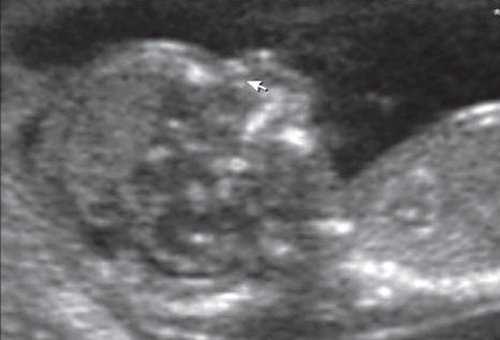

Революцией в пренатальной ультразвуковой диагностике явилось появление объемной эхографии, которая, обладая такими качествами, как неинвазивность, безопасность и возможность многократного применения у одной пациентки, имеет высокую информативность в исследовании анатомии плода и изучении его фенотипа. При применении различных режимов объемной эхографии абсолютно очевидно их преимущество по сравнению с обычным сканированием. Детально можно изучить лицо плода (рис. 1-4) в различные сроки беременности, начиная со сроков первого пренатального скрининга в 11-14 нед, конечности плода, причем не только их наличие и положение (рис. 5, 6), но и состояние и количество пальцев (рис. 7-9) как на руках, так и на ногах. Также можно изучить позвонки плода (рис. 10), состояние твердого нёба (рис. 11, 12), строение наружного уха (ушной раковины) (рис. 13), состояние основных швов черепа и родничков, исключая их преждевременное закрытие при кранисиностозах (рис. 14, 15).

Гипоплазия нижней челюсти при различных нехромосомных синдромах обычно встречается в сочетании со скелетными дисплазиями и мышечно-скелетными аномалиями: синдром Пьера Робена (рис. 3), Тичера - Коллинза (Франческетти), акрофасциальный дизостоз, цереброкостомандибулярный синдром, ахондрогенез (рис. 4), ателостеогенез, кампомелическая дисплазия, диастрофическая дисплазия (рис. 5), синдром множественных птеригиумов, синдром Пены - Шокейра и др. Наличие микрогнатии характерно для синдрома Карпентера, синдрома Фринса, синдрома Меккеля - Грубера, гидролетального синдрома, синдрома Миллера - Дикера, синдрома Нунан, синдрома Секкеля, Рубинштейна - Тейби и др. Большинство из описанных синдромов имеют аутосомно-рецессивный либо аутосомно-доминантный тип наследования [10, 11].